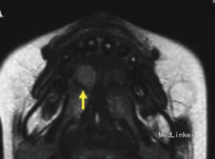

检查发现舌下有一隆起,约1.2*1cm大小,未影响舌功能和运动,唾液分泌正常,周围淋巴结无肿大。 影像检查显示右舌有一不规则圆形肿物,边界不清。

初步诊断为涎腺肿瘤,如多形性腺瘤。然而,由于患者被诊断为共济失调 - 毛细血管扩张症,考虑恶性淋巴瘤的可能性较大。全麻下手术切除,术后配合化疗。病理结果显示为弥漫性大B细胞淋巴瘤。